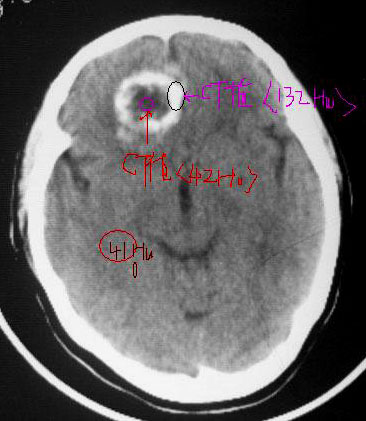

反复头昏1年余...

右额叶内圆形结节状环形钙化块影,周边无水肿.

右前颅窝底圆形钙化影突向额叶内,周围无明显水肿,战位效应轻,考虑脑膜瘤。

平扫前颅底区类圆形骨样高密度影,中心可见低密度影,病变向上生长突入额叶,向下生长突入筛窦,说明病灶来源于额骨水平部,脑膜瘤只能引起颅底骨质的增厚,突入筛窦的几率不大.所以我认为应该首先考虑前颅底骨软骨瘤可能大.如果病变不是来源于颅底骨质,首先应该考虑颅咽管瘤或脑膜瘤.

右前颅窝底圆形钙化影突向额叶内,周围无明显水肿,占位效应轻,考虑脑膜瘤。

前颅窝底肿块,以钙化为主,周围无明显水肿,占位效应轻。考虑:骨软骨瘤或脑膜瘤。